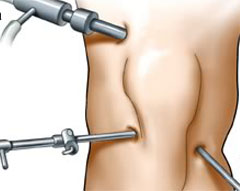

One of the Best Centres in the Bihar offering facilities of Minimally Invasive Orthopaedic Surgery dealing with Joints Replacement Surgery, Arthroscopic Surgery , Sports Surgery and Trauma Surgery using smaller incisions.

The Centre is headed by Dr Bibek Kumar Rai MBBS. DNB (Ortho), D.Ortho, Mch (Ortho), FIMS, MNAMS. Ph.D, Consultant Orthopaedic Surgeon (Joints Replacement & Arthoscopy) who is an eminent figure with over 10 years of Experience in the field of Joint Replacement Surgery & Arthroscopic Surgery ( KEY HOLE SURGERY ) of the Knee & the Shoulder nationally & internationally. He has worked abroad for several years in the field of Joints Replacement Surgery , Sports Medicine & Arthroscopic Surgery.

B K R Advance Orthopaedics Center is one of the Best Centres in the Bihar offering facilities of Minimally Invasive Orthopaedic Surgery dealing with Joint Replacement Surgery , Joint Surgery , Arthroscopic Surgery.

B K R Advance Orthopaedics Center is one of the Best Centres in the Bihar offering facilities of Minimally Invasive Orthopaedic Surgery dealing with Joint Replacement Surgery , Joint Surgery , Arthroscopic Surgery.

B K R Advance Orthopaedics Center is one of the Best Centres in the Bihar offering facilities of Minimally Invasive Orthopaedic Surgery dealing with Joint Replacement Surgery , Joint Surgery , Arthroscopic Surgery.

B K R Advance Orthopaedics Center is one of the Best Centres in the Bihar offering facilities of Minimally Invasive Orthopaedic Surgery dealing with Joint Replacement Surgery , Joint Surgery , Arthroscopic Surgery.